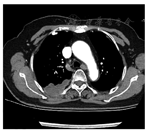

患者,女,77岁,以右后肩背部疼痛2个月为主诉入院,查体无明显阳性体征。胸部CT提示:右肺上叶后段及下叶后部占位,考虑恶性,胸膜起源,邻近胸壁受累,临近肋骨骨折,胸膜增厚、钙化,行经皮胸部肿物穿刺活检术,结果显示:组织部分透明,梭形,束状排列,免疫组化:Vimentin(+),Calretintin(-),Bcl-2(弱+),SMA(-),S-100(-),Ki67(+20%),诊断为(胸壁)交界性或低度恶性间叶源性肿瘤。行手术治疗,开胸进胸腔内见肿物侵袭肺组织及附近胸壁,遂行肿物全切+邻近肺叶切除+被侵袭周围组织切除术,术后的病理显示:肿物切面灰白质硬,浸润肺部,瘤细胞梭形,编制状排列,其间散在炎细胞浸润,见大片变性坏死,免疫组化显示:CK(部分+),Calretintin(局灶+),SMA(+),Ki67(+80%),S-100(-),诊断为(胸壁)炎性肌纤维母细胞瘤。术后4个月患者胸部再次疼痛,再次入院后查胸部增强MR提示炎性母细胞瘤复发,见图1,图2。后于肿瘤内科行放射治疗后右侧胸壁胸膜多发占位及右背部软组织内占位有所缩小,随访患者仍在。